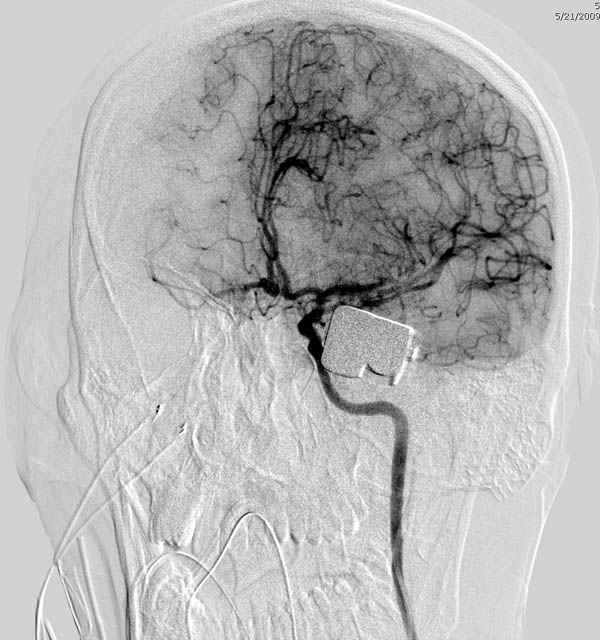

По протоколу сделаны все необходимые исследования: рентген, ангиограмма с 3Д реконструкцией, где обнаружили что все жизненно важные сосуды не задеты, даже некоторые "сидят" изгибаясь на ноже.